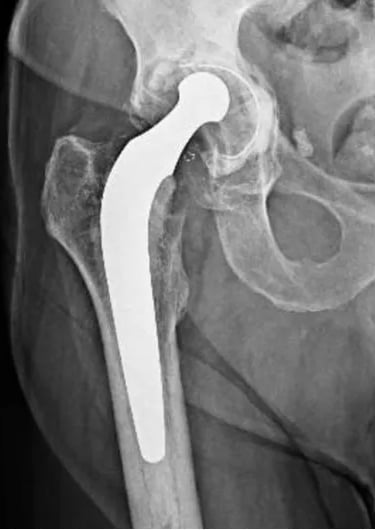

Em casos de desgaste do liner, ele identifica uma assimetria na espessura desse componente, uma vez que o desgaste ocorre na parte de cima apenas, conforme mostrado nas figuras abaixo. A primeira identifica uma prótese com polietileno normal e a segunda, uma com desgaste importante do liner.

Além disso, na presença de soltura da prótese, o RX também faz o diagnóstico, mostrando uma linha escura ao redor dos componentes da prótese (por conta da perda óssea nessa região) e/ou uma alteração do posicionamento dos componentes, quando comparado aos RX antigos

Essas imagens de RX são de modelos antigos de prótese de quadril, nas quais a qualidade dos materiais era muito inferior às disponíveis atualmente. Dessa forma, o desgaste nessas próteses era muito mais rápido e frequente, fazendo com que a durabilidade dessas próteses não fosse muito longa, em torno de 12 a 15 anos. Com o desenvolvimento das cabeças de cerâmica e liners de polietileno cross-linked, a durabilidade aumentou significativamente, para 25 a 30 anos.